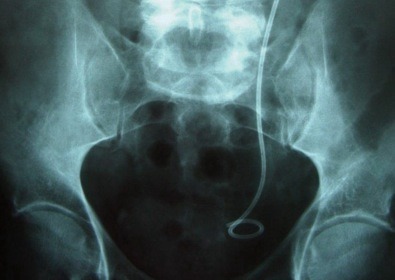

c est une sonde qui m a ete placée lors de ma derniere operation du rein , pour une pyélonéphrite et donc cette sonde aide le rein a bien faire son travail , elle est placée du rein à la vessie .donc elle m a ete placée sous anesthesie general .

Normalement il y a un systeme de valve sur l'uretère à l'entrée de la vessie.

Comme la sonde est en place cette valve est constament ouverte ... donc l'urine remonte dans l'uretère. Ca donne de drole de sensations.

De plus tu as vu la forme de cette sonde ... pas très glamour ... elle pèse sur les parois du rein et de la vessie.